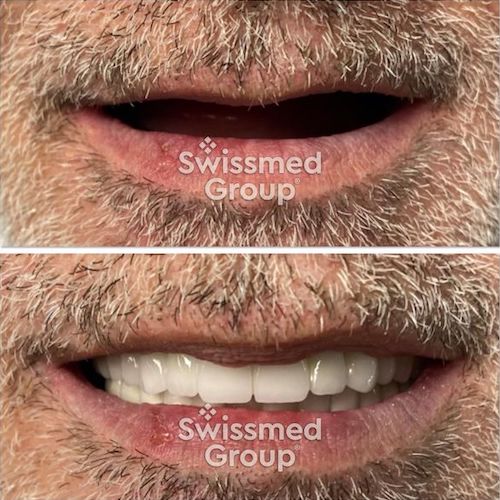

SMILE DESIGN

Estetik diş hekimliği denilince akla gelen ilk kavramlardan biri ''gülüş tasarımı''dır. Gülüş tasarımı; çeşitli nedenlerle estetik açıdan görünümü bozulan dişler ve diş etlerinin hastaların yüz şekilleri ve gereksinimleri de göz önünde bulundurularak olabildiğince doğal ve güzel bir görünüme kavuşturulması işlemidir. Multidisipliner bir yaklaşım olan gülüş tasarımı, birçok işlemin bir arada uygulanmasıyla gerçekleştirilmektedir.

Diş hekimliğinde hastalara gerçekçi, doğal görünümlü gülümsemeler vermek için özel seramikler kullanılmaktadır. IPS E-Max, diğer diş restoratiflerinden farklı olarak gücü ve güzelliği birleştiren seramik bir malzemedir.Tamamen seramikten yapılmış diş restorasyonları metal içermez. Bu nedenle, ışık doğal dişlerde olduğu gibi içlerinde ve Magical Touch sayesinde parlayabilir.

Magical Touch kusursuzluğa ulaşan diş laboratuvarı hizmeti sunmayı hedeflemektedir. Gün geçtikçe gelişen hizmetleri, teknoloji altyapısı ve uzman kadrosu sayesinde geleceğe ve globalleşmeye emin adımlarla ilerlemektedir.